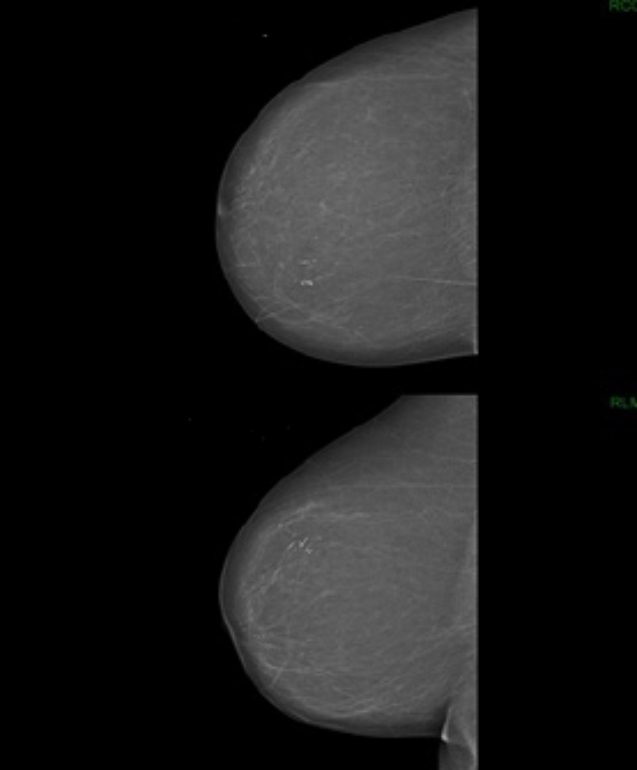

La mammographie montre l’aspect suivant.

Question 4 - Vous tirez les conclusions suivantes :

Il s’agit du quadrant supéro-interne, ce qui correspondait par ailleurs plus à la clinique.

On voit une anomalie (microcalcification) et la mammographie est donc à classer au moins ACR2. Par ailleurs, cette mammographie serait probablement classée ACR5.

Il faut réaliser une micro-biopsie (ou macro-biopsie si la lésion est difficilement palpable).

Pour rappel, concernant la classification de l’American College of Radiology (ACR) sur l’aspect d’une mammographie :

– ACR1 : mammographie normale ;

– ACR2 : anomalie bénigne (pas de surveillance ni d’examen complémentaire) ;

– ACR3 : anomalie probablement bénigne à surveiller : surveillance à court terme (mammographie à 3-6 mois) ou biopsie ;

– ACR4 : anomalie suspecte nécessitant une histologie → microbiopsie ou macrobiopsie selon la situation ;

– ACR5 : lésion d’allure maligne → microbiopsie ou macrobiopsie.

Par ailleurs, pour la lecture d’une mammographie, il faut retenir les repères suivants :

– sur le cliché de face : quel que soit le sein, la partie supérieure du sein représente le quadrant externe, et la partie inférieure représente le quadrant interne ;

– sur le cliché oblique externe : au-dessus du mamelon = quadrants supérieurs, en-dessous = quadrants inférieurs.

Ci-joint un cliché pour vous aider à comprendre cette mammographie :